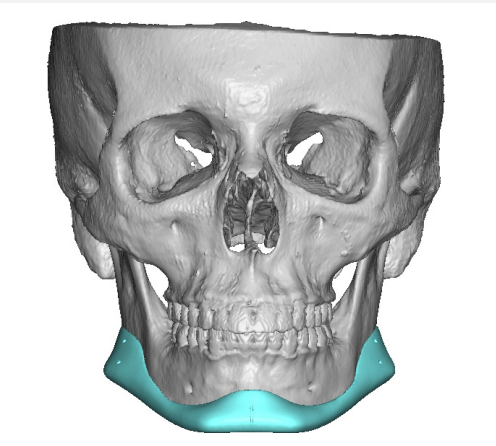

Recieved the draft 1 of the design, what changes should i ask for?? a couple of things i can think of are malar implants not giving enough lateral protrusion, gonion flaring.

I also am planning to include infra implants as well.